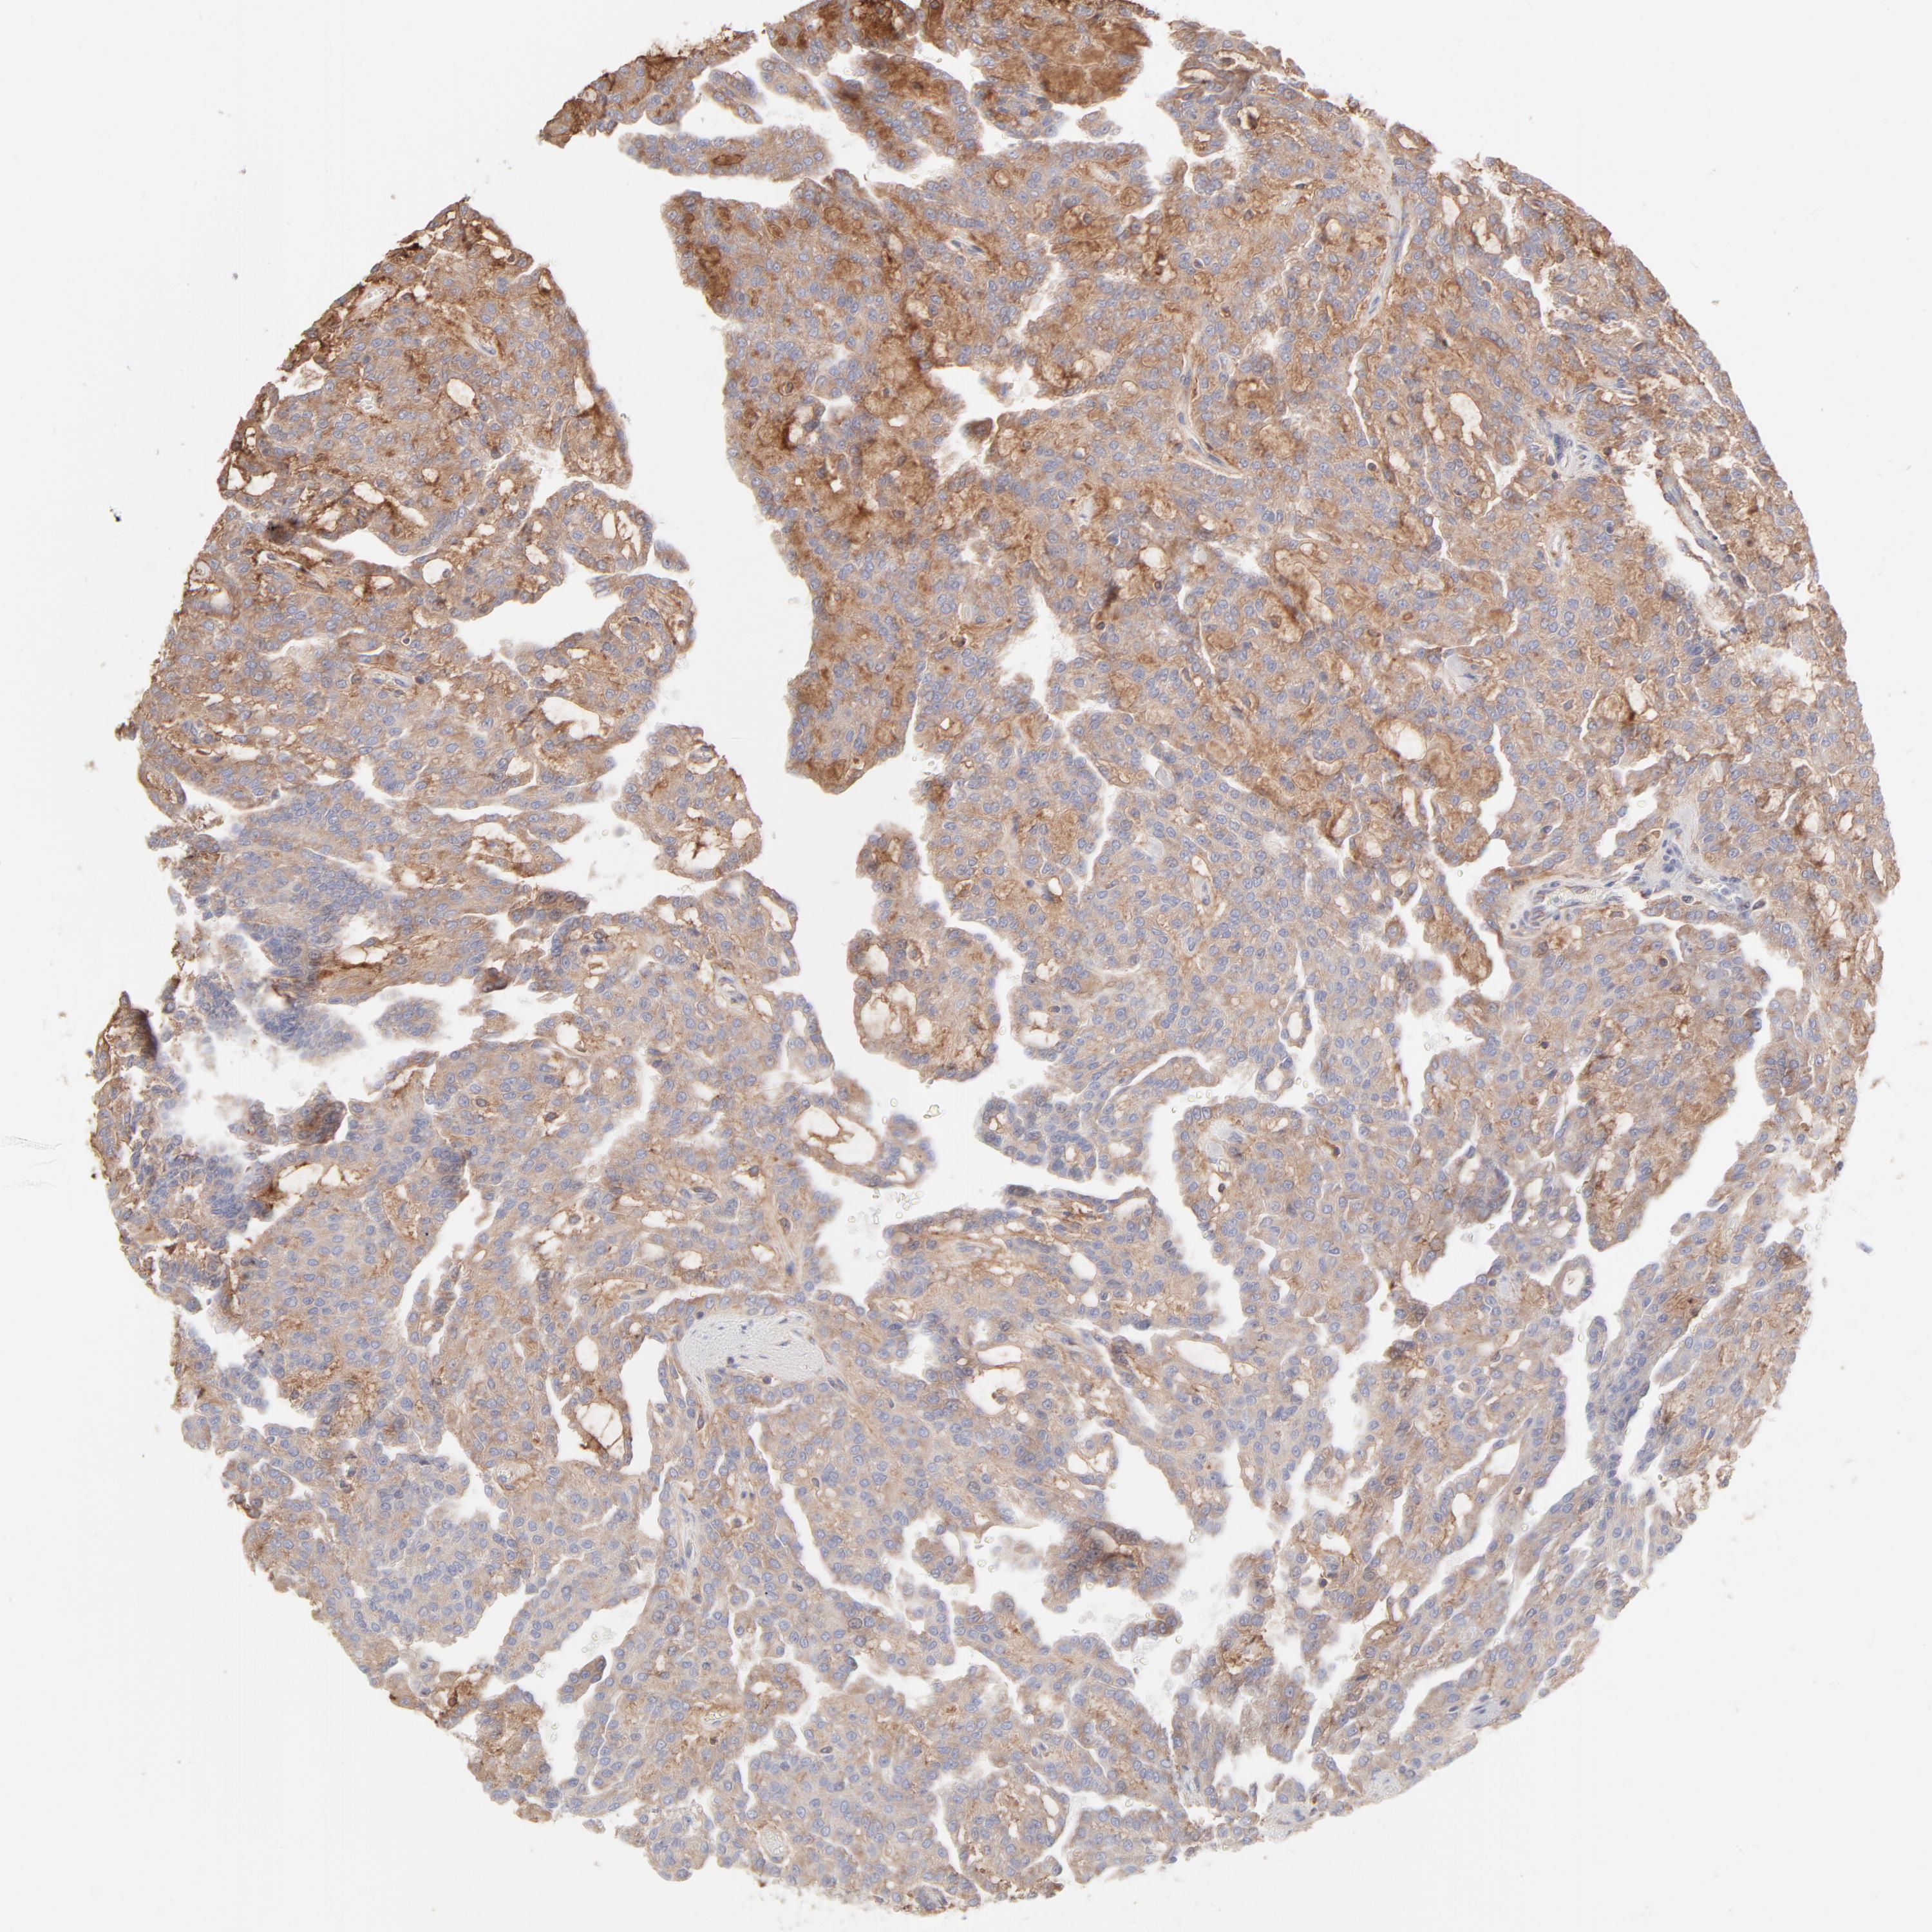

KIDNEY RENAL CLEAR CELL CARCINOMA (VALIDATION) - Interactive survival scatter ploti

The Survival Scatter plot shows the clinical status (i.e. dead or alive) for all individuals in the patient cohort, based on the same data that underlies the corresponding Kaplan-Meier plots. Patients that are alive at last time for follow-up are shown in blue and patients who have died during the study are shown in red.

The x-axis shows the expression levels (FPKM) of the investigated gene in the tumor tissue at the time of diagnosis. The y-axis shows the follow-up time after diagnosis (years). Both axes are complimented with kernel density curves demonstrating the data density over the axes. The top density plot shows the expression levels (FPKM) distribution among dead (red) and alive patients (blue). The right density plot shows the data density of the survived years of dead patients with high and low expression levels respectively, stratified using the cutoff indicated by the vertical dashed line through the Survival Scatter plot. This cutoff is automatically defined based on the FPKM cutoff that minimizes the p-score. The cutoff can be changed by dragging the vertical line or by entering a cutoff value in the square labeled "Current cut-off".

Under the Survival Scatter plot the p-score landscape (black curve; left axis) is shown together with dead median separation (red curve; right axis). Dead median separation is the difference in median mRNA expression between patients who have died with high and low expression, respectively. It is calculated as follows: median FPKM expression of dead patients with high expression - median FPKM expression of dead patients with low expression. This is intended to aid the user in visually exploring custom cutoffs and the associated p-scores and dead median separation.

Individual patient data is displayed and can be filtered by clicking on one or more of the category buttons on the top of the page. Categories describing expression level and patient information include: high, low, alive, dead, female, male and tumor stages. The scale of the x-axis can be toggled between linear and log-scale by clicking on the "x log" button. Mouse-over function shows TCGA ID, patient information and mRNA expression (FPKM) for each patient.

& Survival analysisi

Kaplan-Meier plots summarize results from analysis of correlation between mRNA expression level and patient survival. Patients were divided based on level of expression into one of the two groups "low" (under cut off) or "high" (over cut off). X-axis shows time for survival (years) and y-axis shows the probability of survival, where 1.0 corresponds to 100 percent.

RPS21 is not prognostic in Kidney Renal Clear Cell Carcinoma (validation)

Best expression cut offi

Based on the FPKM value of each gene, patients were classified into two groups and association between prognosis (survival) and gene expression (FPKM) was examined. The best expression cut-off refers the FPKM value that yields maximal difference with regard to survival between the two groups at the lowest log-rank P-value. Best expression cut-off was selected based on survival analysis .

When clicking on this number, the vertical dashed line indicating cut-off, the interactive survival plot, and the Kaplan-Meier curve will be adjusted to show results based on the best expression cut-off.

: 2251.72

P scorei

Log-rank P value for Kaplan-Meier plot showing results from analysis of correlation between mRNA expression level and patient survival.

N/A

Average pTPM 1868.6

Number of samples 100